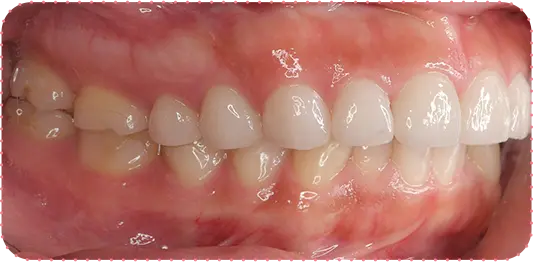

主訴

前歯をきれいにしたい

治療期間

8か月

治療費

40万円

治療内容

右上2番をマウスピース矯正で移動してラミネートべニアにて修復

治療のリスク

【マウスピース】

矯正装置を初めて装着した時は、違和感や圧迫感、疼痛などを感じる場合があります。

歯根吸収や歯肉の退縮が起こる場合があります。

1日の装着時間が長いため、口内清掃不足だとむし歯・歯周病のリスクが高くなります。

歯の移動後に保定装置(リテーナー)の使用が不十分の際は、後戻りが生じる場合があります。

マウスピースの装着時間が少ないと治療期間が長引く場合があります。

【セラミック】

咬み合わせによっては、セラミックが欠ける可能性があります。